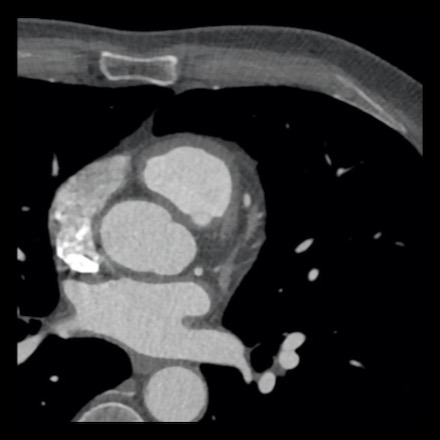

case 2 – CAD-RADS 5/P2/S

First, scroll through the CTA images.

How would you describe the findings on the coronary CTA?

The findings are:

- Stent in the mid

LAD with low-attenuation within the stent suggestive of minimal in-stent

restenosis (<25%). Non-calcified plaque distal to the stent

causing mild stenosis (25-49%). Notice bridging on a short segment in

the distal LAD. - Non-calcified

plaque in the LCX causing mild stenosis (25-49%). - Occlusion of the

proximal OM1 branch with distal filling. - Calcified and

non-calcified plaques in the proximal RCA causing mild (25-49%) stenosis. - Total plaque burden

is moderate based on SIS (four segments including proximal RCA, mid LAD, prox

LCX and OM1).

Due to the occlusion of OM1 branch and presence of the stent, this case

reads as CAD-RADS 5/P2/S, which means that this patient needs further

diagnostic workup.